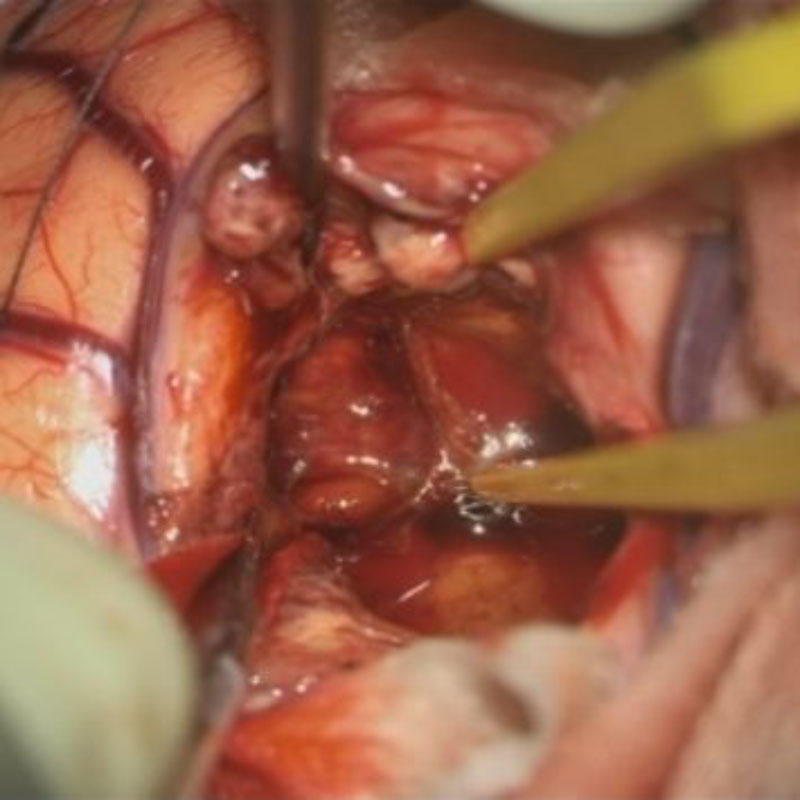

術中写真

摘出 中